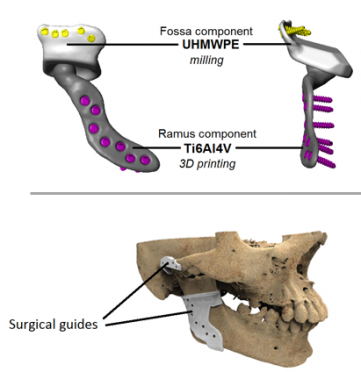

In total TMJ replacement, the condyle and part of the ramus are replaced with a custom prosthetic component. The purpose of that surgery is obviously functional reconstruction severe TMJ disease, ankylosis, degeneration, failed prior surgery, things like that not aesthetics.

First, TMJ prostheses are designed around function first. Joint mechanics, fixation, occlusion, loading, range of motion, and long term stability matter far more than trying to create extra width. So even if something is possible geometrically, that does not automatically make it a good design choice.

As patient specific reconstruction keeps improving better imaging, better CAD/CAM planning, better biomaterials, better prediction of soft tissue response I think this whole area could become more refined.

Reference images to my previous points:

In total TMJ replacement, the condyle and part of the ramus are replaced with a custom prosthetic component. The purpose of that surgery is obviously functional reconstruction severe TMJ disease, ankylosis, degeneration, failed prior surgery, things like that not aesthetics.

First, TMJ prostheses are designed around function first. Joint mechanics, fixation, occlusion, loading, range of motion, and long term stability matter far more than trying to create extra width. So even if something is possible geometrically, that does not automatically make it a good design choice.

As patient specific reconstruction keeps improving better imaging, better CAD/CAM planning, better biomaterials, better prediction of soft tissue response I think this whole area could become more refined.

Reference images to my previous points: